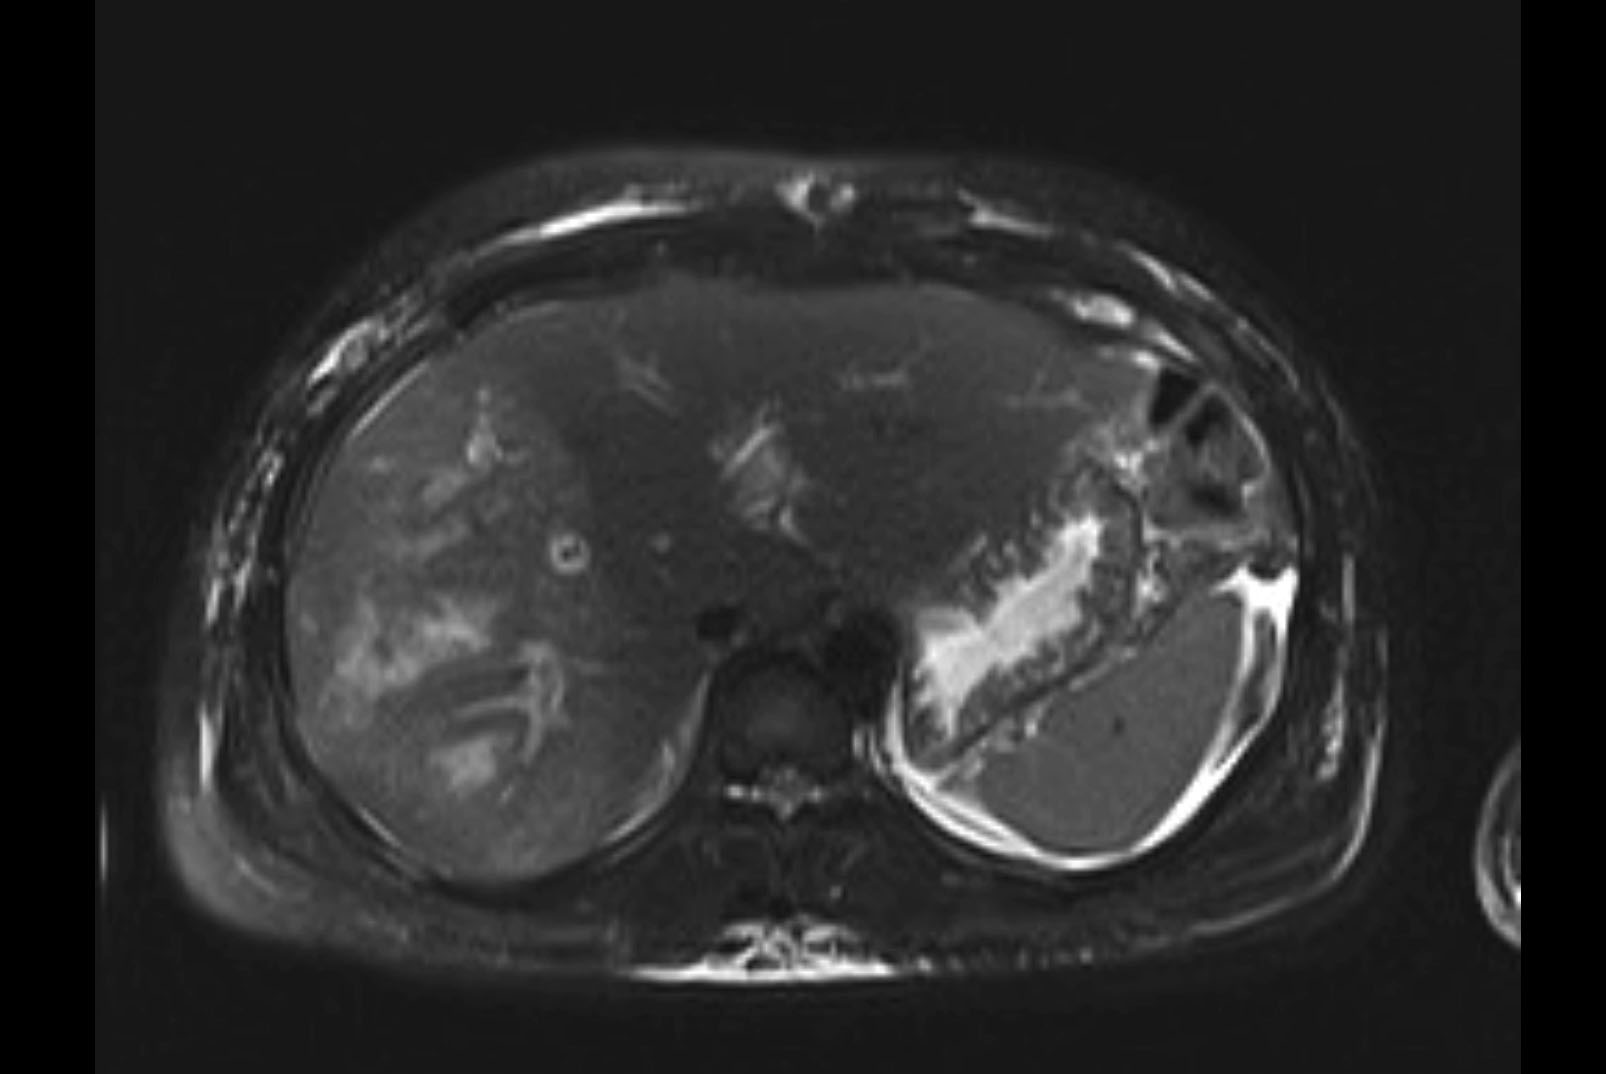

MRI T1

MRI T2